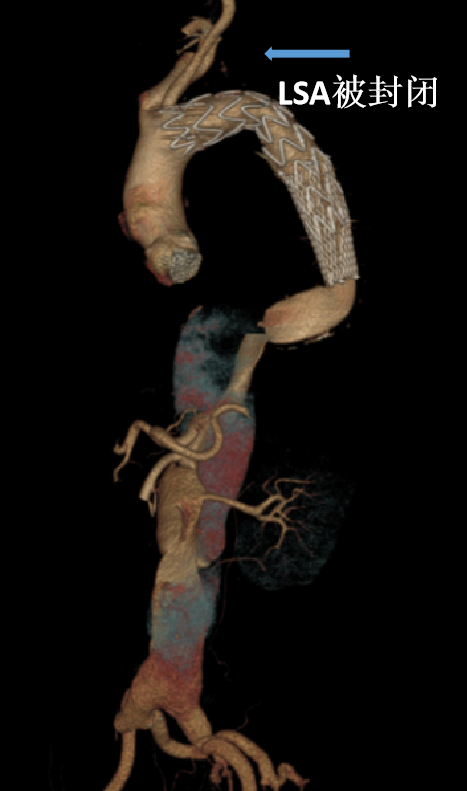

LSA被封闭,升主置换术后:

弓部三根动脉均移位到升主